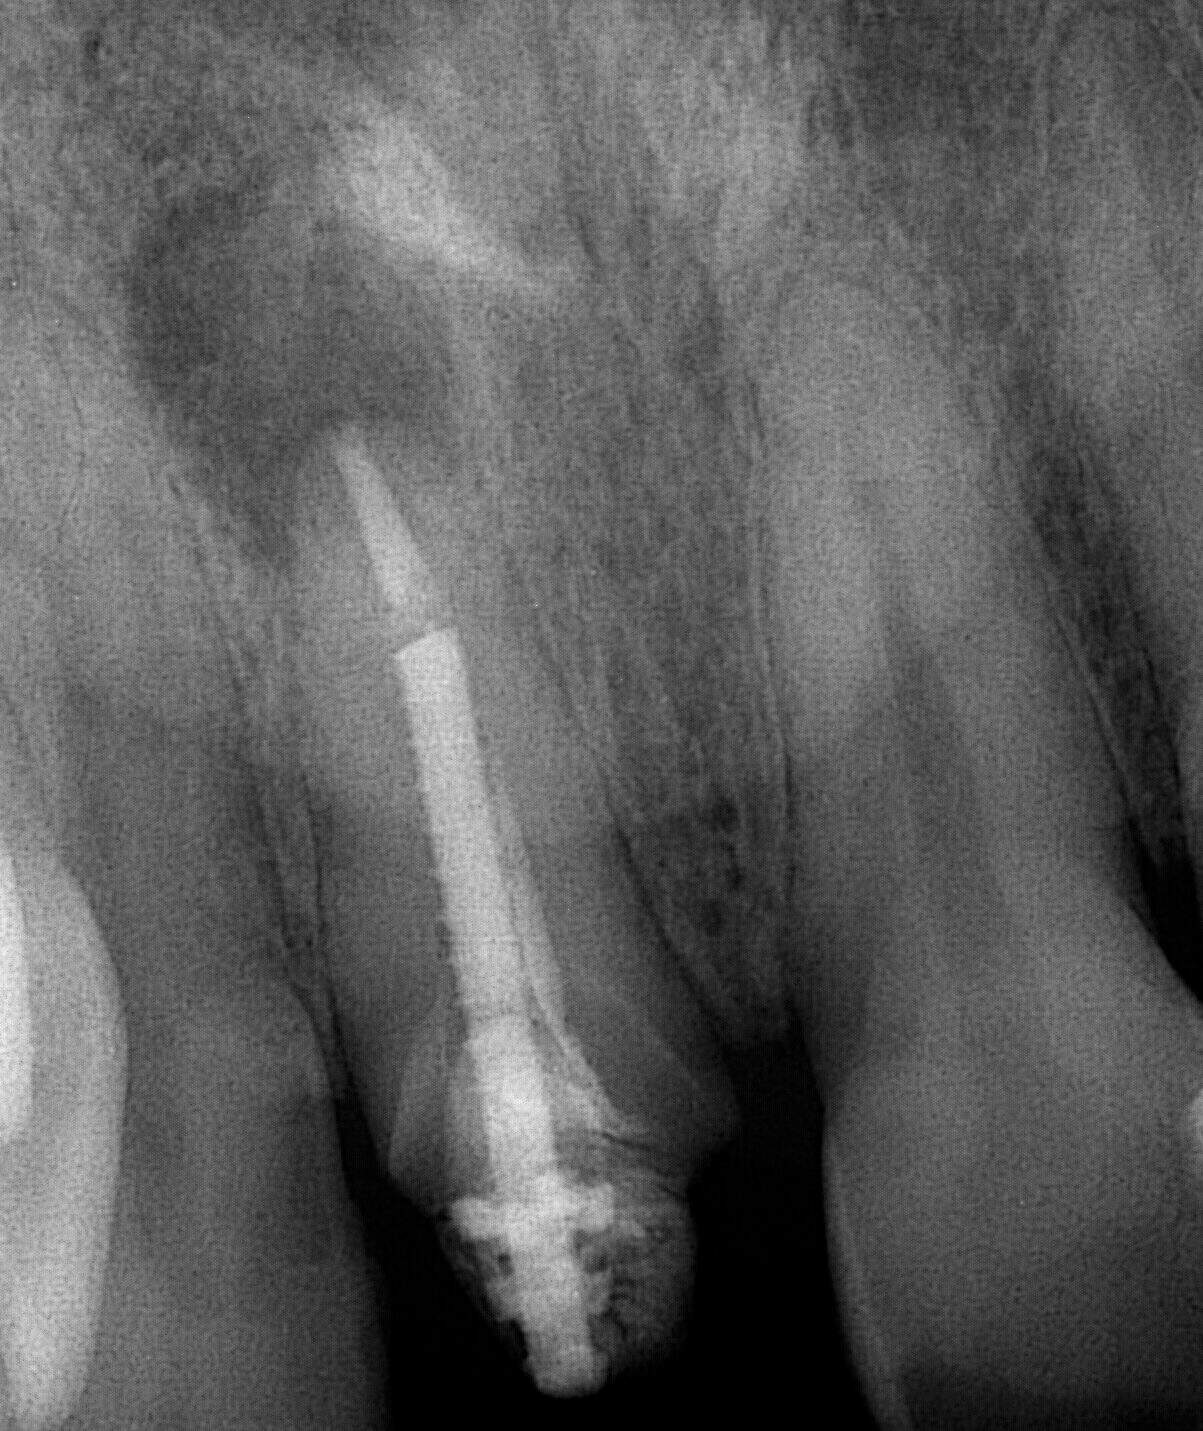

Our patient returned after his tooth was disinfected by a root canal specialist (Endodontist.) Dr. Peter Mann then placed a Rescue post in the tooth which will help hold the crown.

A digital impression was then taken with our Itero scanner for a porcelain crown. The patient left our office with a temporary crown held in place by the new post.